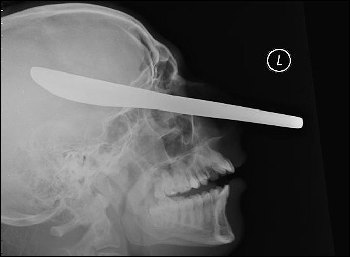

一把用來抹黃油的刀就這樣插在了受害人邁克爾的頭部。

當(dāng)醫(yī)生向邁克爾展示這張恐怖的頭部X光片時(shí),他不敢相信自己的眼睛——一把用來抹黃油的刀從他的左側(cè)臉頰穿過,直達(dá)他右側(cè)的頭蓋骨,距離他的大腦只有1英寸(約2.5厘米)。

在庭上,法官尤伊斯特說:“我看過那張X光片,我只能用惡心和震驚來形容看到照片的感覺。我不能理解一個(gè)人怎么可以如此惡毒,做出這樣的事情。你(馬克)對(duì)社會(huì)沒有任何貢獻(xiàn),你必須一輩子都處于警方監(jiān)管之下?!?/p>